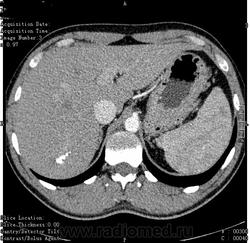

- https://radiomed.ru/sites/default/files/styles/case_slider_image/public/user/16314/ct.1.002.jpg?itok=n00uCisV

- https://radiomed.ru/sites/default/files/styles/case_slider_image/public/user/16314/ct.1.005.jpg?itok=tL-o0Zyd

- https://radiomed.ru/sites/default/files/styles/case_slider_image/public/user/16314/ct.1.006.jpg?itok=eD2B8PpJ

- https://radiomed.ru/sites/default/files/styles/case_slider_image/public/user/16314/ct.1.009_0.jpg?itok=t616c8pc

- https://radiomed.ru/sites/default/files/styles/case_slider_image/public/user/16314/ct.1.013.jpg?itok=naYfaJaK

- https://radiomed.ru/sites/default/files/styles/case_slider_image/public/user/16314/ct.1.016.jpg?itok=7QI04EsU

- https://radiomed.ru/sites/default/files/styles/case_slider_image/public/user/16314/ct.1.017.jpg?itok=EJmrsm0z

- https://radiomed.ru/sites/default/files/styles/case_slider_image/public/user/16314/ct.1.019.jpg?itok=KMCM7VHI

- https://radiomed.ru/sites/default/files/styles/case_slider_image/public/user/16314/ct.1.020.jpg?itok=m1jAA0ZW

- https://radiomed.ru/sites/default/files/styles/case_slider_image/public/user/16314/ct.1.021.jpg?itok=i89Jb3je

- https://radiomed.ru/sites/default/files/styles/case_slider_image/public/user/16314/ct.1.025.jpg?itok=UWwwyZZY

- https://radiomed.ru/sites/default/files/styles/case_slider_image/public/user/16314/ct.1.026.jpg?itok=FQfAszqG

- https://radiomed.ru/sites/default/files/styles/case_slider_image/public/user/16314/ct.1.027.jpg?itok=qJa3vYdf

- https://radiomed.ru/sites/default/files/styles/case_slider_image/public/user/16314/ct.1.028.jpg?itok=LjsabUNE

- https://radiomed.ru/sites/default/files/styles/case_slider_image/public/user/16314/ct.1.031.jpg?itok=cV37-2V6

- https://radiomed.ru/sites/default/files/styles/case_slider_image/public/user/16314/ct.1.032.jpg?itok=MrYi5Lda

- https://radiomed.ru/sites/default/files/styles/case_slider_image/public/user/16314/ct.1.033.jpg?itok=t7V0JYJY

- https://radiomed.ru/sites/default/files/styles/case_slider_image/public/user/16314/ct.1.038.jpg?itok=qu-97Yhs

- https://radiomed.ru/sites/default/files/styles/case_slider_image/public/user/16314/ct.1.039.jpg?itok=-aeLLBFV

Не понятно, вроде инородные тельца. Либо кальцинаты. Образования в печени не вижу. А какое тут может быть заключение, кроме кальцинатов? Признаков сосудистой опухоли (флеболиты) или любой иной опухоли , паразитарной кисты не вижу.

Кальцинаты в печени редкое явление. Вопрос мало изучен. Теоретически это последствие перенесенной инекции. Есть вариант, что могут метазстазы обызвествляться. Но в практике таких тотально кальцинированых метастазов не видел. Так что, если ничего не беспокоит, взять на контроль и забыть.

Ну, природа кальцинатов в печени может быть очень различна.

но вообще если они не сочетаются или не являются компонентами допонительных образований, характер которых требует уточнения, не увеличиваются при динамическом наблюдении и не находятся внутри желчных протоков - про них можно забыть.

"Although a wide variety of causes of hepatic calcification has been described (Table 1), the most common causes are calcified granulomas and hydatid cysts, followed by calcification as- sociated with hepatic neoplasms (3). Other ori- gins of calcification include vascular and biliary causes. "